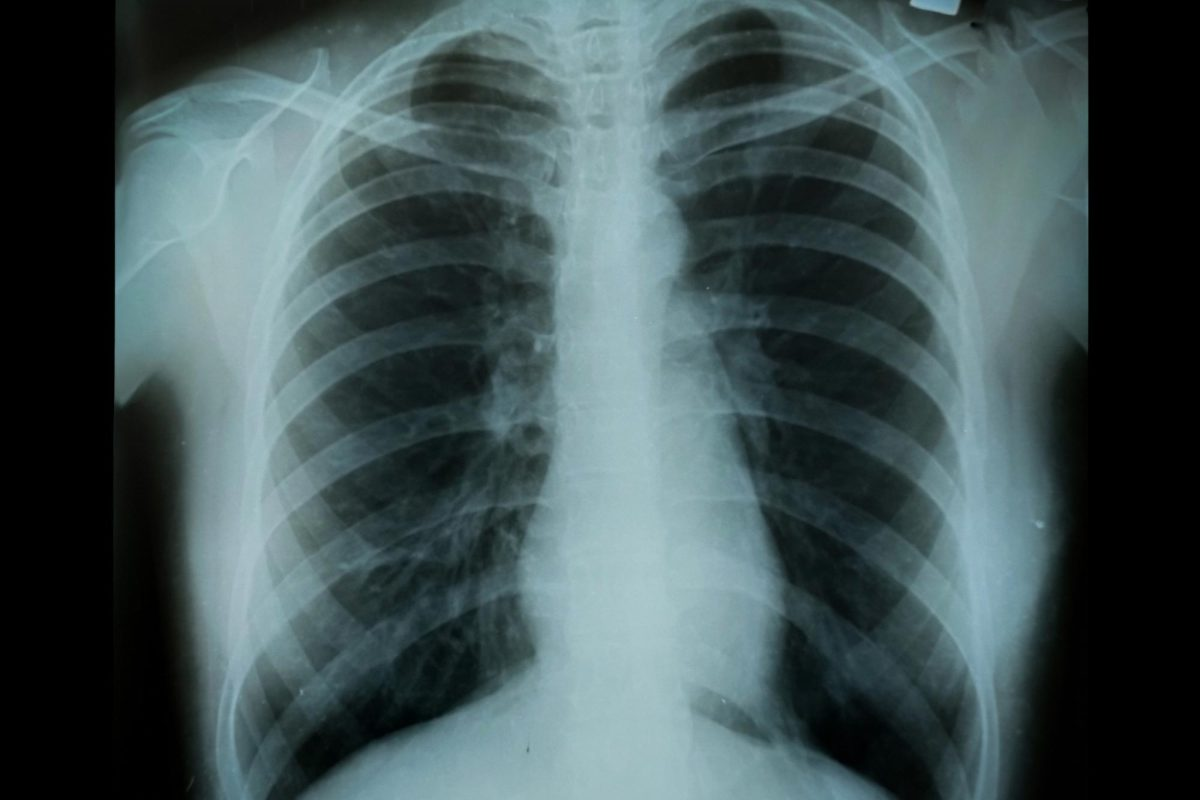

In the past, doctors mainly used spirometry to check lung function. Spirometry helped figure out how severe COPD was by looking at the forced expiratory volume in one second (FEV1). But, this method had its limits. It didn’t fully show how COPD affects people’s lives.

Limitations of Spirometry-Only Classification

Using spirometry alone had big problems. It didn’t take into account the different ways symptoms can affect people. This made treatment plans not always right for each patient.